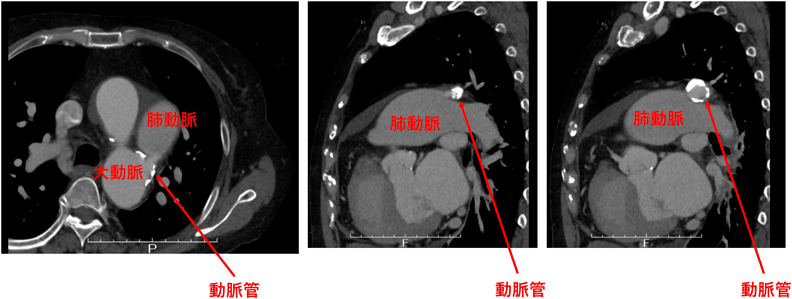

Fig. 5 心不全精査中に動脈管開存が判明した60代女性

左室拡大(LVDd/Ds 62/44 mm)も認め,閉鎖適応と判断.動脈管に石灰化を認めるが,Amplatzer Duct Occluder (ADO)で閉鎖が可能であった.